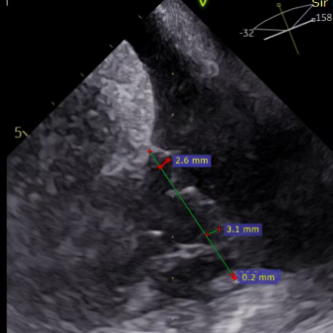

Ultrasound Evaluation:

- Type valve with type IIIb quadricuspid malformation and severe insufficiency (mean vena contracta: 7.4mm).

- Regurgitation orifices located at the anteroseptal and posteroseptal commissures, with a 5.7×3.3mm gap detected in the center.